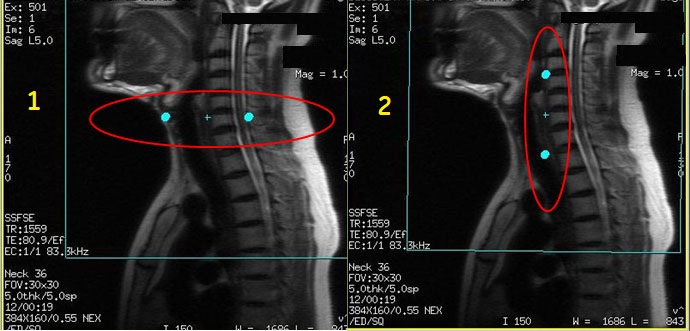

Figure 1. PROPELLER and FSE comparison

Table 1. Image legend

NumberDescription

1PROPELLER images

2FSE images